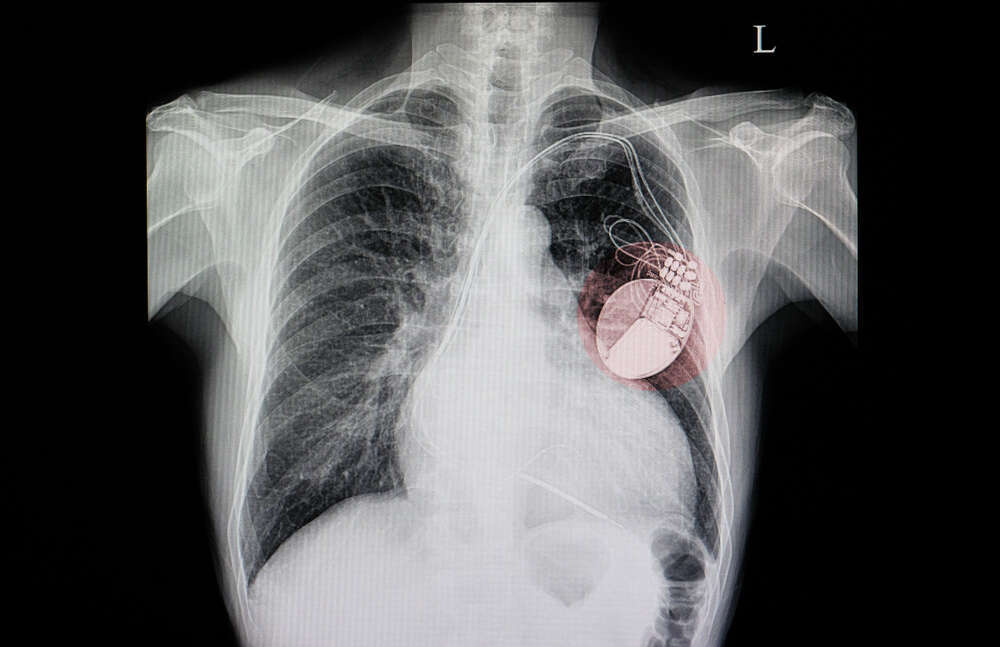

קוצב לב. | צילום: שאטרסטוק